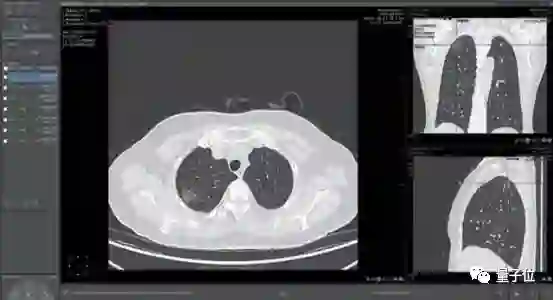

除了之前提到的临床应用Streams,他们还开发了可以筛查乳腺癌和识别50多种眼疾的技术。

医疗影像辅助诊断是当时医疗AI公司扎堆投入的领域。这家公司最大的卖点肺结节诊断,则是红海中的红海。

一家医院接入4、5家AI肺结节诊断产品成了司空见惯,曾有影像医师笑称:

中国人的肺结节都不够用了。